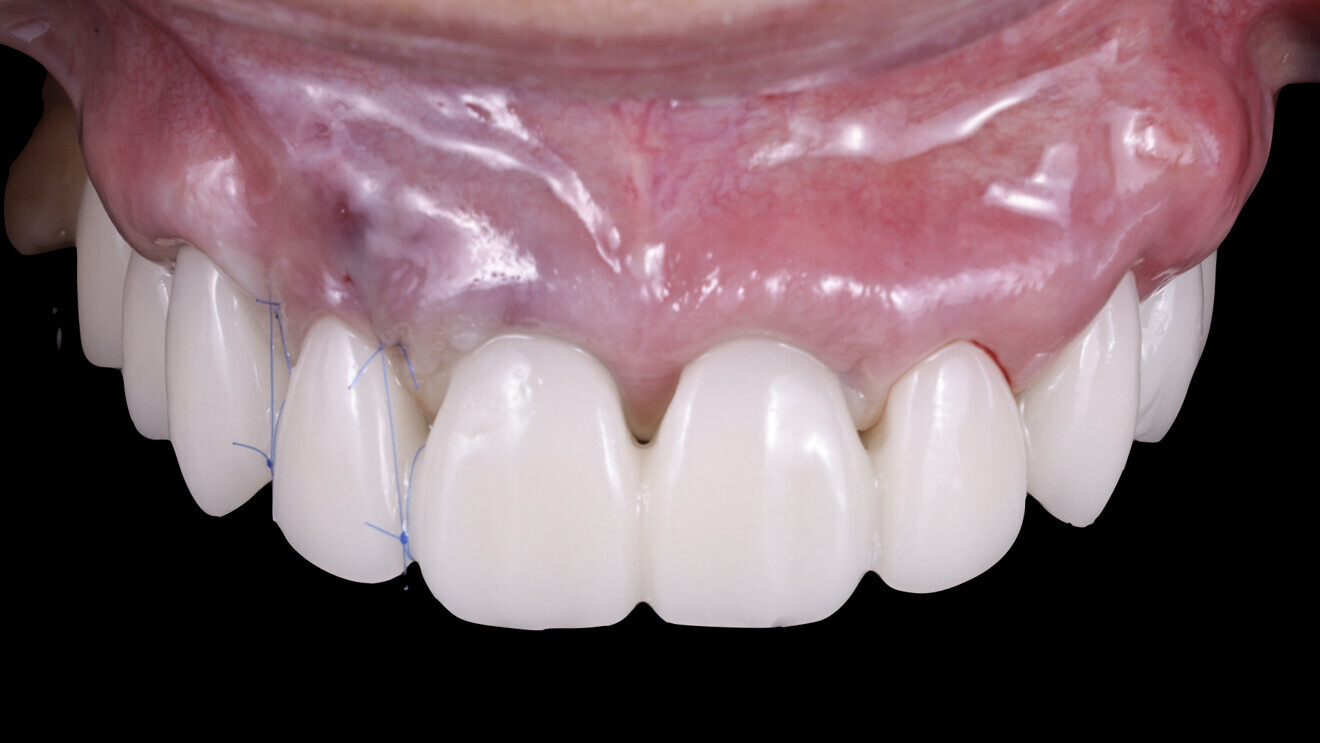

Fig. 22: After delivery of the temporary restoration the day after implant placement.

Delivery of the temporary restoration and healing phase

The following day, a connective tissue graft was placed in the area of tooth #12 to enhance the soft-tissue profile, and the temporary restoration was delivered. After the delivery, the patient was allowed to heal for a period of four months, allowing for proper implant integration and soft-tissue healing (Figs. 19–22).